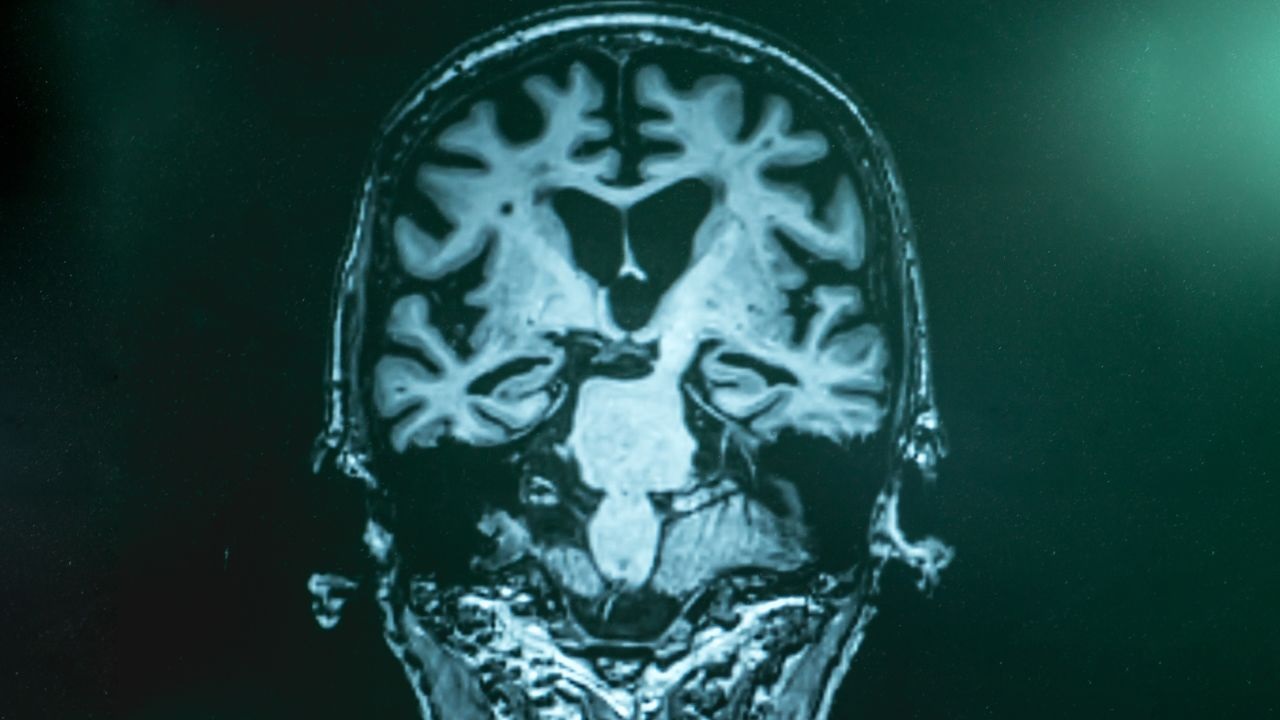

Ερευνητές από το Πανεπιστήμιο της Καλιφόρνιας στο Ίρβαϊν διερεύνησαν τον τρόπο με τον οποίο οι μορίων που υπάρχουν στη διατροφή επηρεάζουν την υγεία των νευρώνων. Η μελέτη τους, που δημοσιεύθηκε στο GeroScience, αποκαλύπτει ότι η νικοτιναμίδη και η γαλλική επιγαλλοκατεχίνη επίδρασαν στην παραγωγή ενέργειας στα εγκεφαλικά κύτταρα. Αυτές οι ενώσεις, που προέρχονται από τη βιταμίνη Β3 και το πράσινο τσάι, δοκιμάστηκαν σε νευρώνες από ποντίκια.

Τα εργαστηριακά πειράματα έδειξαν αποκατάσταση των επιπέδων τριφωσφορικής γουανοσίνης, ενός μορίου-κλειδιού για την κυτταρική ενέργεια. Αυτή η ανάκαμψη επέτρεψε στους νευρώνες να επανενεργοποιήσουν τους μηχανισμούς καθαρισμού τους, ιδιαίτερα την αυτοφαγία, η οποία εξαλείφει τα απόβλητα πρωτεϊνών. Τα συσσωματώματα αμυλοειδούς, χαρακτηριστικά της νόσου, μειώθηκαν σημαντικά μετά από μόλις είκοσι τέσσερις ώρες θεραπείας.

Η ομάδα χρησιμοποίησε έναν γενετικά κωδικοποιημένο αισθητήρα φθιρίου που ονομάζεται GEVAL για να παρατηρήσει τις αλλαγές σε πραγματικό χρόνο. Διαπίστωσαν ότι η μείωση της ενέργειας στα μιτοχόνδρια, τα εργοστάσια παραγωγής ενέργειας των κυττάρων, αντιστράφηκε. Αυτή η μη φαρμακευτική προσέγγιση θα μπορούσε να προσφέρει μια εναλλακτική λύση στις συμβατικές θεραπείες, στοχεύοντας άμεσα στην πηγή του ενεργειακού προβλήματος.

Ο μελετητής Gregory Brewer τονίζει ότι αυτή η μέθοδος αποκαθιστά βασικές κυτταρικές λειτουργίες που χάνονται με την ηλικία. Ωστόσο, προειδοποιεί να μην εφαρμοστεί αμέσως. Προηγούμενες κλινικές δοκιμές έχουν δείξει απενεργοποίηση της νικοτιναμίδης στο αίμα, γεγονός που απαιτεί βελτιωμένες συνθέσεις.

Αυτή η έρευνα ανοίγει το δρόμο για νέες θεραπευτικές στρατηγικές βασισμένες σε συμπληρώματα διατροφής. Υπογραμμίζει τη σημασία των ενεργειακών μορίων όπως το GTP, που συχνά παραβλέπονται σε μελέτες για νευροεκφυλιστικές ασθένειες. Απαιτείται επιπλέον εργασία για τη βελτιστοποίηση της χορήγησης και την επικύρωση της αποτελεσματικότητας σε ανθρώπους.